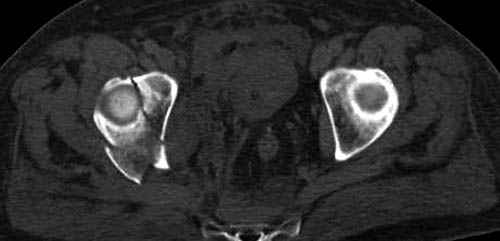

Дополнительно имеется перелом ацетабулума: задняя

колонна с полупоперечным переломом, и переломы костей лица.

На седьмой день зафиксирован перелом ацетабулума через задний доступ. Перед операцией для профилактики DVT, IVC фильтер, также получает Lovenox.

Извиняюсь за качества снимков, обычный больной в 300 фунтов, портативным ренген аппаратом не пробить.

Там множество обычных 2.7 мм шурупов, потом идет фиксация основными пластинами.

Снимки здесь....